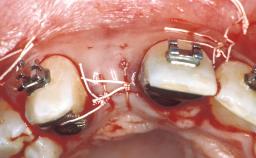

In September of 1995, a 64-year-old female patient presented to our clinic with a distally shortened arch in the left maxilla and the desire for a fixed rehabilitation. The patient’s medical history did not reveal any major issues, and she did not take any significant medication. She was a non-smoker and did not report any allergies.The patient wished to restore her chewing function on the left side, which was severely compromised due to the missing teeth 25, 26, and 27. The antagonistic lower teeth were present and in acceptable condition.